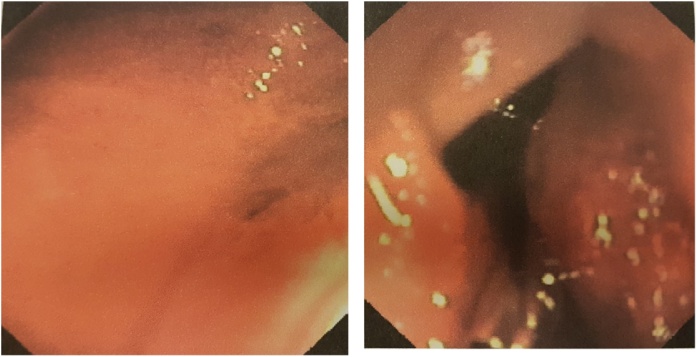

Fig. 2.

a, b: EGDS demonstrated an active bleeding from ulceration of the mass (a) and positioning of two titanium clips to perform haemostasis (b).

She had several episodes of haematochezia and melena. Clinical examination showed a skin pallor and tachycardia but normotension. Physical examination of the abdomen was negative except for typical café-au-lait spots as well as multiple skin nodules. Digital rectal examination showed cherry red stool with blood clots followed by dark stool. Blood tests showed haemoglobin 7.3 g/dl, red cells 2.37 × 106 and haematocrit 20.8. An abdominal Computed Tomography (CT) scan was initially negative. She was transferred to the medical department. The patient then underwent an EGDS which showed evidence of an upper digestive haemorrhage at the level of a mass, with ulceration in the third duodenum without active bleeding. The following day the patient experienced further melena and blood clots, but with normal vital signs. An abdominal Contrast-Enhanced Computed Tomography (CECT) and abdomen CT angiography (CTA) revealed a hyperdense mass of third duodenum, diameter 33 × 24 mm and no active bleeding (Fig. 1a, b). After another episode of melena and blood clots with hypotension, we performed a second EGDS that demonstrated an active bleed from ulceration of the mass in the third duodenum (Fig. 2a, b). Haemostasis was performed using two titanium clips. She received two units of packed red cells. Angiography confirmed the tumoral neoangiogenesis and no blushing of contrast (no active bleeding) (Fig. 3a, b).